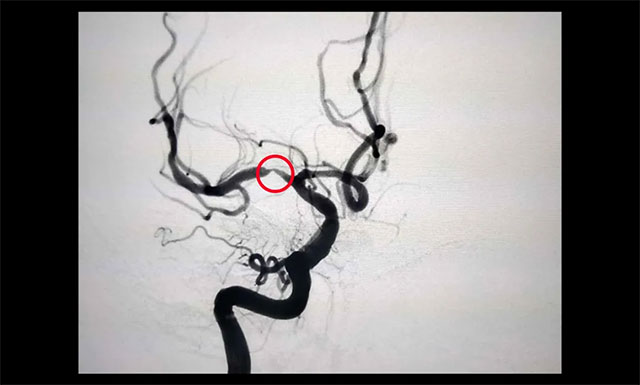

▲ 患者右侧大脑中动脉M1段重度狭窄

经行 DSA 检查,胡老伯右侧椎动脉纤细,右侧大脑中动脉 M1 段重度狭窄(约80%-90%),只剩下不到20%的空间,血流明显受阻。李振并主任表示,大脑中动脉是颈内动脉的延续,它供应大脑外侧面3/4的血液,所以大脑中动脉狭窄后会导致部分区域血流不足而引起相关症状。严重时会出现偏身运动障碍、偏身感觉障碍,甚至昏迷。一般情况下,当大脑中动脉狭窄程度超过70%,需要及时进行支架植入治疗,同时要注意其他危险因素的预防。